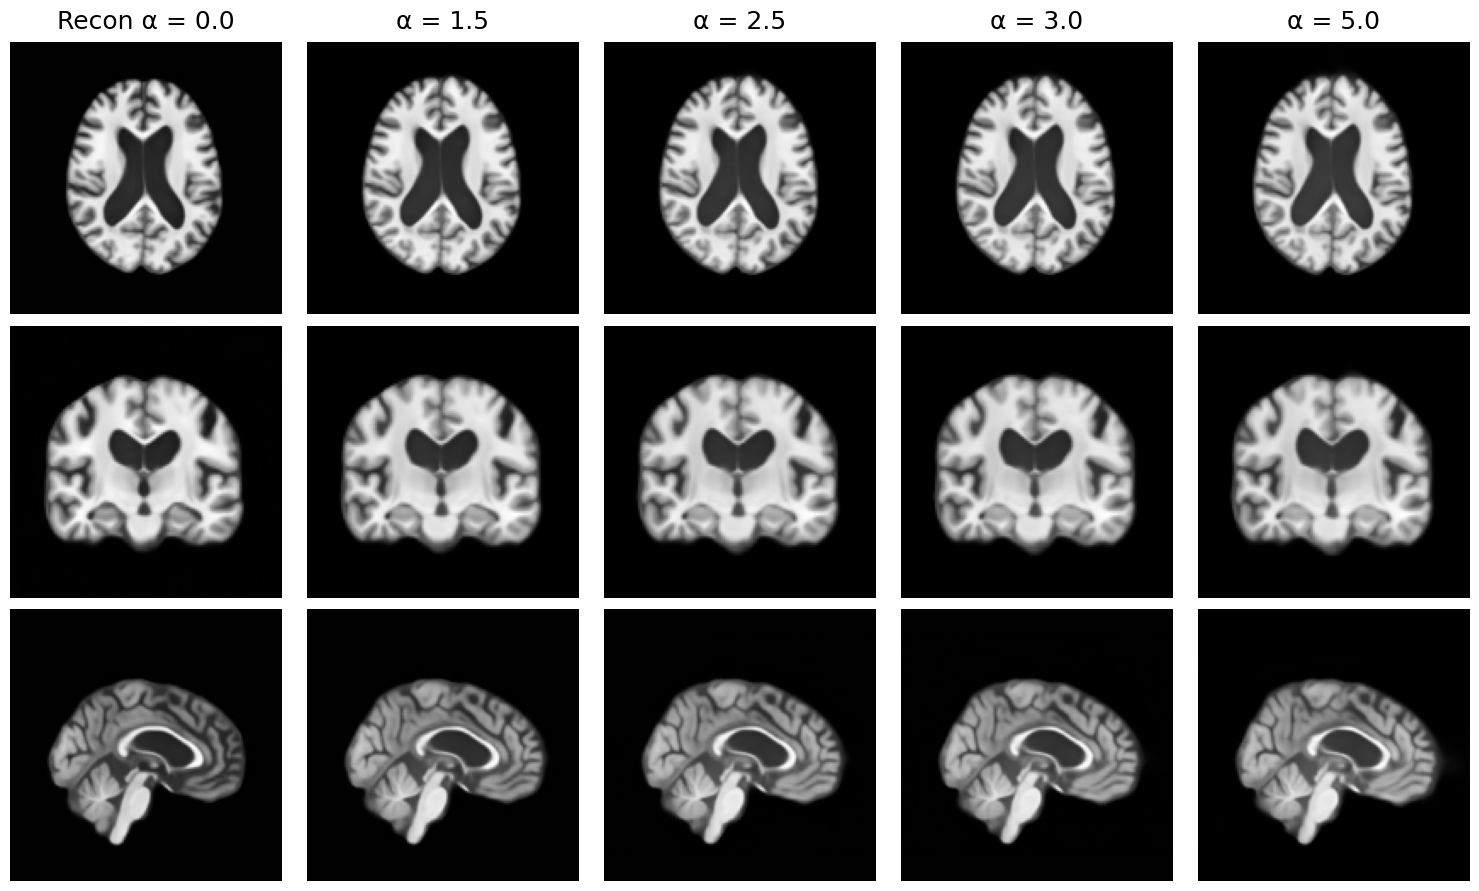

5.4.1 Semantic Manipulation via Latent Directions

To qualitatively evaluate the interpretability and controllability of the learned semantic space, we conducted a semantic manipulation experiment following the strategy discussed in Section 3.7. Once a linear classifier is trained to distinguish between AD and CN subjects using the semantic representations , its weight vector defines the principal direction along which the most discriminative semantic variation lies. Since the classifier is trained with label 0 assigned to AD and 1 to CN, moving along amplifies AD-related features (manipulating CN towards AD). In contrast, moving in the opposite direction reduces them (manipulating AD towards CN). Given a subject’s scan, we perform the manipulation as follows:

Figure 6 shows the effect of different manipulation strength, we progressively increased from 0.0 to 5.0 for an AD subject. The anatomical changes become increasingly pronounced as grows, particularly in hippocampal and ventricular regions, highlighting a smooth and meaningful trajectory in the latent space. Figure 7 shows two representative examples: in the first case (top), an AD subject is manipulated along the direction towards a CN-like representation, and in the second (bottom), a CN subject is manipulated along the direction towards an AD-like representation. Both manipulations use a scaling factor .